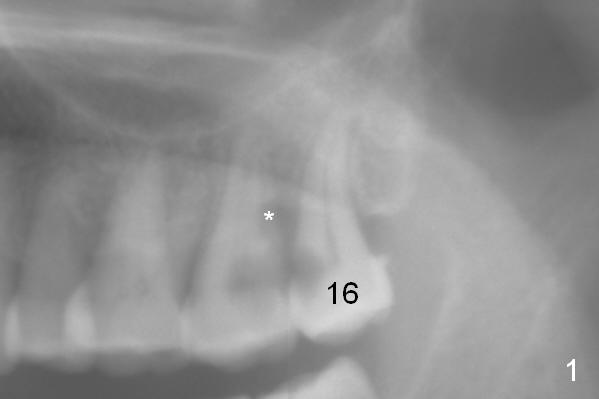

A 53-year-old woman has toothache in the upper left sextant. It appears that the teeth #15 and 16 are non-salvageable due to proximal root caries (Fig.1 *). The tooth #15 is extracted first and the socket will be packed with 2% Xylocaine, 1:50,000 Epinephrine gauze. The decay at #16 will be removed to reduce intraop contamination (Fig.3 *), followed by insertion of a piece of gauze (Fig.3 white). Rounded tapered (RT) osteotomes (Fig.3 red arrow) or drills will be used for sinus lift (Fig.1 ^: sinus floor). With the 3rd molar temporarily in site, the trajectory of the osteotomy is easily controlled.